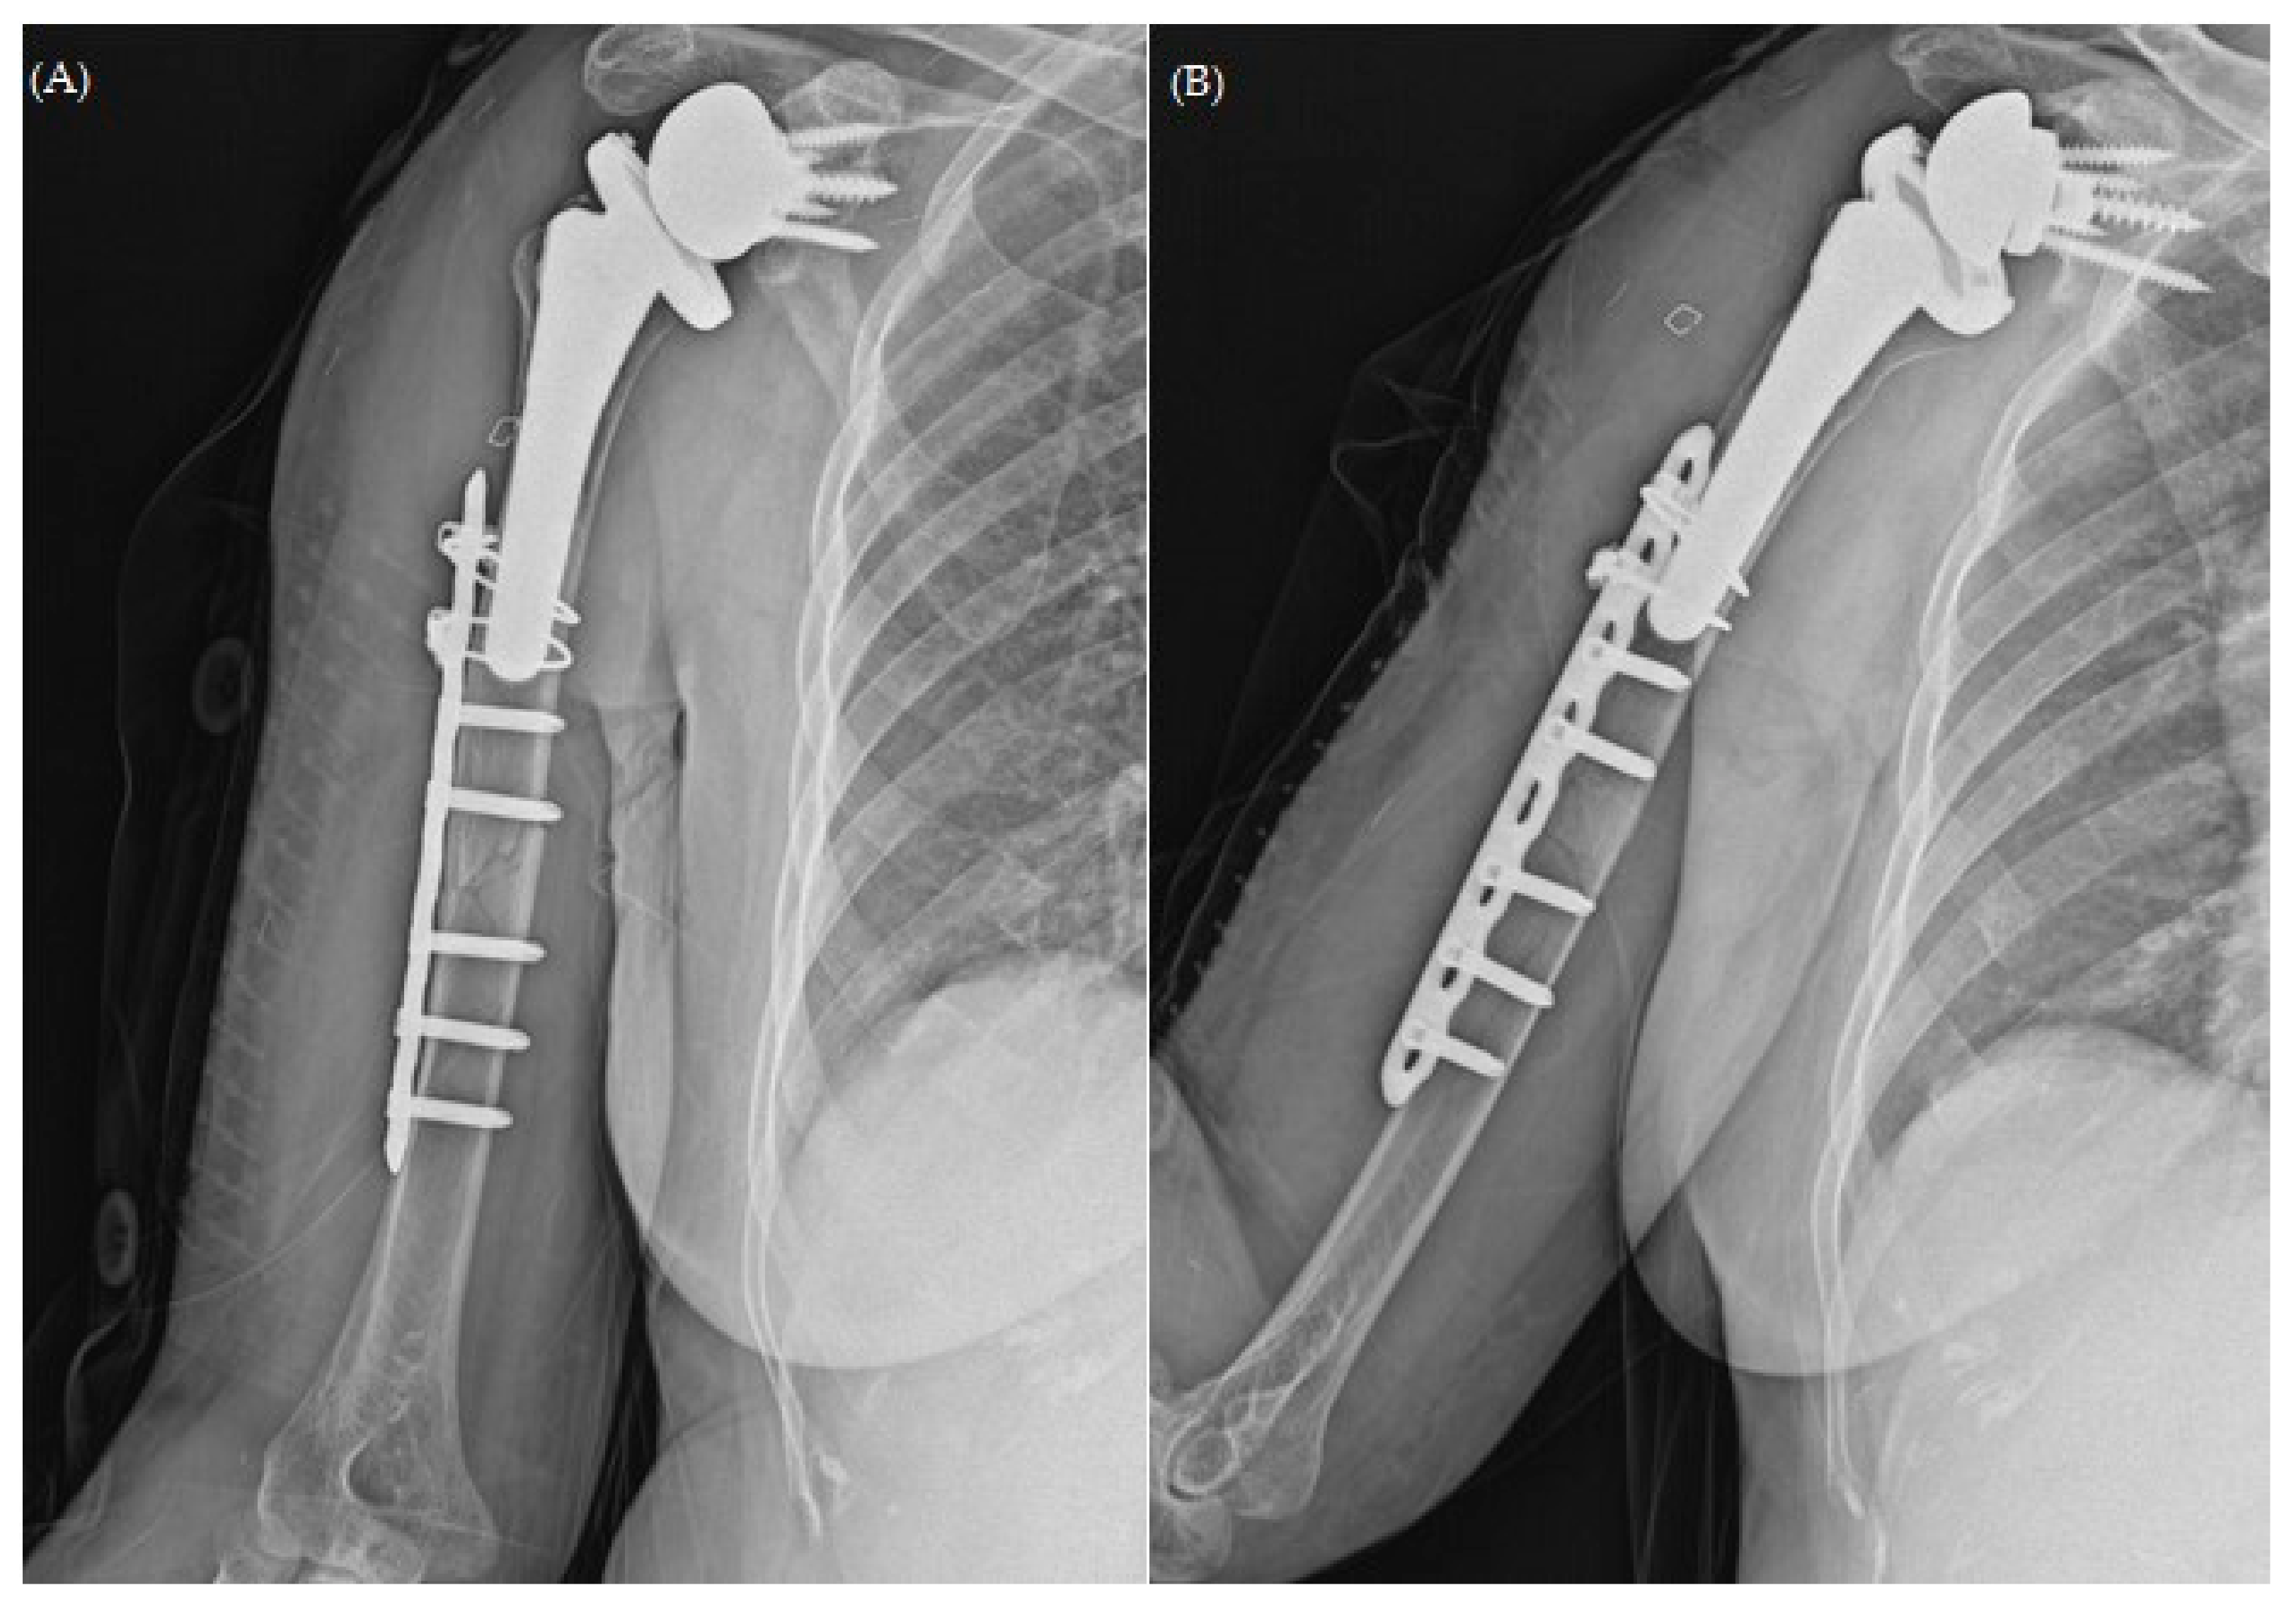

Figure 2. Plain radiographs of humerus (A) AP; (B) lateral views after open reduction and plate osteosynthesis for periprosthetic fracture.

After undergoing osteosynthesis at a nearby orthopedic clinic 9 months before (Figure 2), the patient experienced persistent chronic pain, prompting her visit at our outpatient clinic during the follow-up. Apart from hypertension, she had no relevant medical history. Physical examination suggested no tenderness but showed severe limitations in the range of motion (ROM) due to pain.